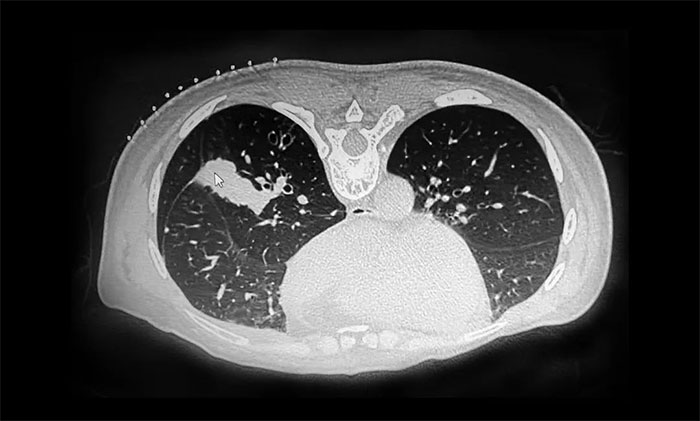

近日,张泽明主任成功开展一例CT引导下经皮肺穿刺活检术。53岁女性患者陆某(化名)有乳腺癌病史,近期反复咳嗽、咳痰就医,行肺部CT检查提示肺部多发占位。

▲ CT检查提示肺部多发占位

由于患者肺部病变位置靠近外周,气管镜下难以取得病变部位标本。经医院肿瘤科(放疗)、十楼重症监护病房、医学影像科开展多学科讨论,并经反复评估后,决定行CT引导下经皮肺穿刺活检,以明确诊断。